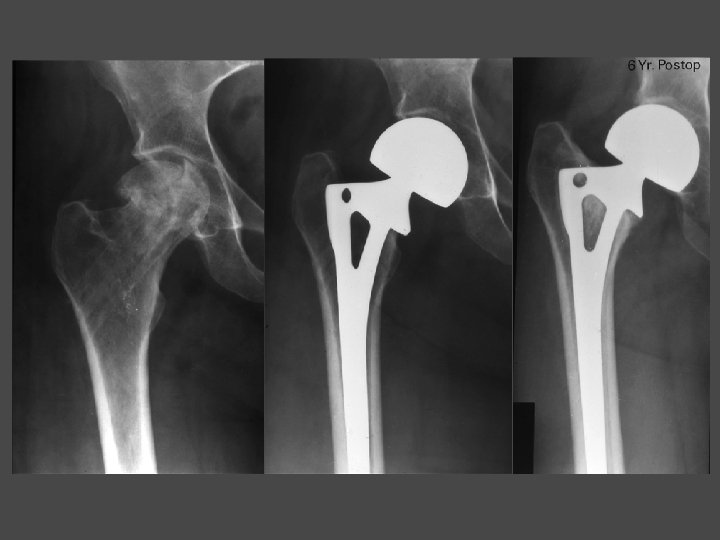

6 yrs PR

OSTEONECROSIS - ARTHROPLASTY Bipolar • Abandoned • No advantages over THA • Main reason for failure is groin pain